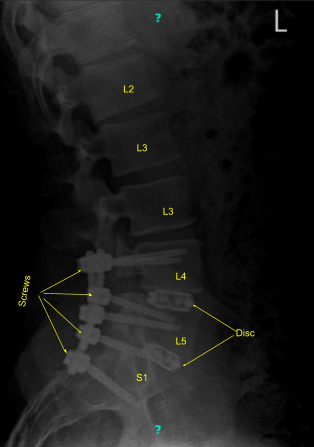

MRI and CT of Lumbar spine were done which showed degenerative disc disease L4-5 and L5-S1 with re-herniation at L4-5.

Aero was brought in and a spin was done to obtain CT scan images. The navigation reference was verified. Having navigation ready, pedicle screws were planned to be inserted first on the left L4 followed by right L4, left L5, right L5, left S1, and right S1 sequentially.

All the entry points were marked with the reference probe followed by drill, followed by navigator gear shift, navigator tip and insertion of pedicle screws on bilateral L4, bilateral L5, and bilateral S1.

After that, a low dose CT scan with Aero was again done to confirm the placement of the screws and the cage. The newly taken pictures showed satisfactory positions of all the six pedicle screws and the cages x 2. Further adhesions of both bilateral L4,bilateral L5, and bilateral S1 nerve roots were released with the use of Penfield and Woodson tool.